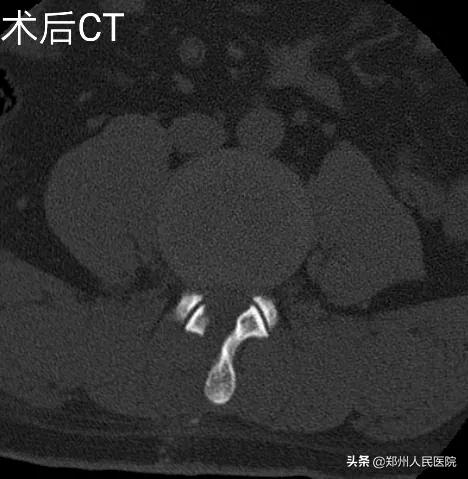

经过充分准备,对小葛实施的“单侧双通道UBE脊柱内镜术”如期举行。手术进行的十分顺利,经过一个半小时,手术成功。

为刘叔进行的“单侧双通道UBE脊柱内镜术”在不足两个小时后顺利结束,术中麻醉效果极佳,出血量只有数十毫升,清晰放大的视野下,突出的髓核及增厚的黄韧带完全摘除,骨性狭窄磨钻安全扩大减压,偶尔出现的小出血点也在射频刀头的控制下立即止血,轻松漂浮的神经根又重新出现了。

UBE技术即单侧双通道内镜技术(Unilateral Biportal Endoscopy Technique),利用多裂肌与棘突间的潜在间隙形成三角式的对流关系以保持良好灌注冲洗获取清晰术野,适用于颈、胸、腰椎退行性病变。

相对于发展比较成熟的椎间孔镜技术及后路椎板间入路单通道内镜技术,该技术通常建立两个通道,一个为观察通道,一个器械操作通道。